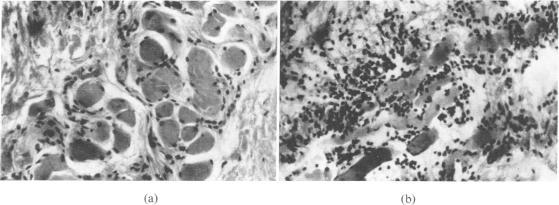

Pathological findings are reported on 34 specimens from 16 cases of arthrogryposis multiplex congenita (AMC), including initial observations on paraffin sections from 28 muscles, and subsequent observations on six additional specimens from three of these cases studied both histologically and histochemically. Thirteen of the 34 specimens (from 11 cases) were histologically normal, probably on account of an unaffected muscle being sampled. The most constant pathological feature in the remaining specimens was a disorganization of the muscle fibres and fascicles by severe fibrosis; only three specimens (from two cases) did not show this. Very thin faintly striated muscle fibres embedded in this matrix were encountered in 10 specimens from nine cases. An attempt at grouping of these atrophic or ill-developed fibres was noticed in four specimens; but this may not be denervation atrophy. Two specimens (from two cases) showed `myopathic' features. Repeat biopsy after two to three years was carried out on two affected muscles each from three patients. Case 3 showed well preserved but uniformly small fibres. Case 4 showed extremely few and scattered small rounded fibres. Case 14 showed pronounced variation of fibre size in both, with both atrophic and hypertrophied fibres. Normal nerves and spindles were seen in all these six specimens irrespective of the state of the muscle, and excessive fibro-fatty tissue in cases 4 and 14. Histochemical examination for oxidative enzymes, ATPase, and phosphorylase in these six specimens revealed a normal checkerboard pattern and ratio of type I and type II fibres, in case 3 only. The muscles of case 4 showed a preponderance of type I fibres. One specimen from case 14, showed the same fibres reacting for both oxidative enzymes and phosphorylase, suggesting a lack of development of fibres. The intrafusal fibres were mainly of type I in all. Two possible pathogenetic mechanisms operating in early embryonic life, which may lead to the characteristic changes of AMC, are discussed: (1) a defect in the development of the muscle whereby the full recruitment of myoblasts from the mesenchyme of the limb-bud does not take place and muscles do not form adequately; (2) a lack of innervation of the muscles on account of arrested growth of anterior horn cells. The combined operation of both these mechanisms is also considered. Fibrous tissue replaces the muscle tissue that is lacking, and contractures and deformities ensue. The evidence gathered on our material, such as the very thin smooth muscle fibres, the large numbers of well-formed nerves and spindles especially in the repeat biopsies, and the above-mentioned histochemical feature, would appear to favour the hypothesis of ill-developed muscles in the production of AMC in the majority; in the rest denervation playing either a major or concurrent role.